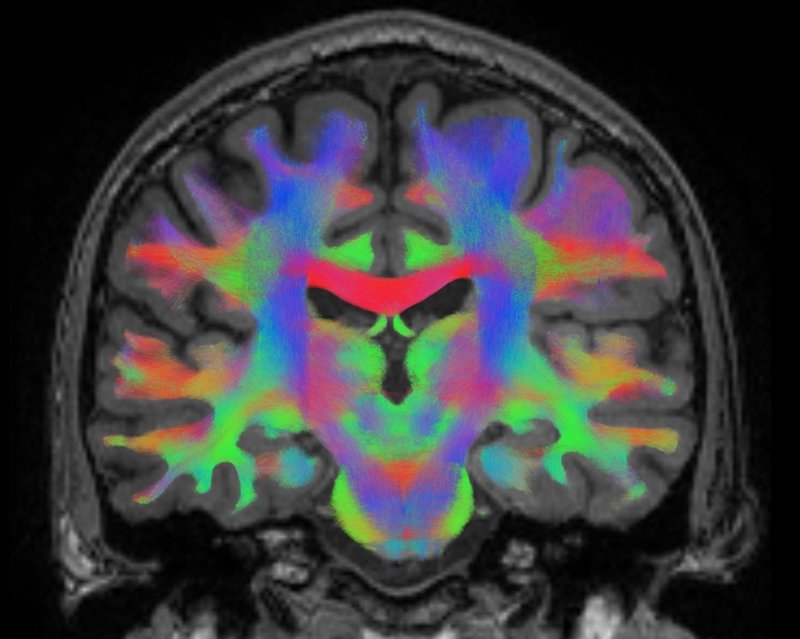

Un total de 16 astronautas se someterán a escáneres de resonancia magnética avanzada antes y después de sus vuelos al espacio, con el objetivo de detectar cualquier cambio en su estructura cerebral.

Los expertos sospechan que los cerebros de los astronautas se adaptan a vivir en condiciones de ingravidez mediante el uso de enlaces sin explotar entre las neuronas. Es decir, quieren saber cómo es el cerebro humano y cómo cambia cuando los astronautas aprenden a flotar alrededor en su nave espacial, de izquierda a derecha y de arriba hacia abajo. Unos movimientos que son "una segunda naturaleza" para el astronauta y que, se cree, activará nuevas conexiones en su cerebro.